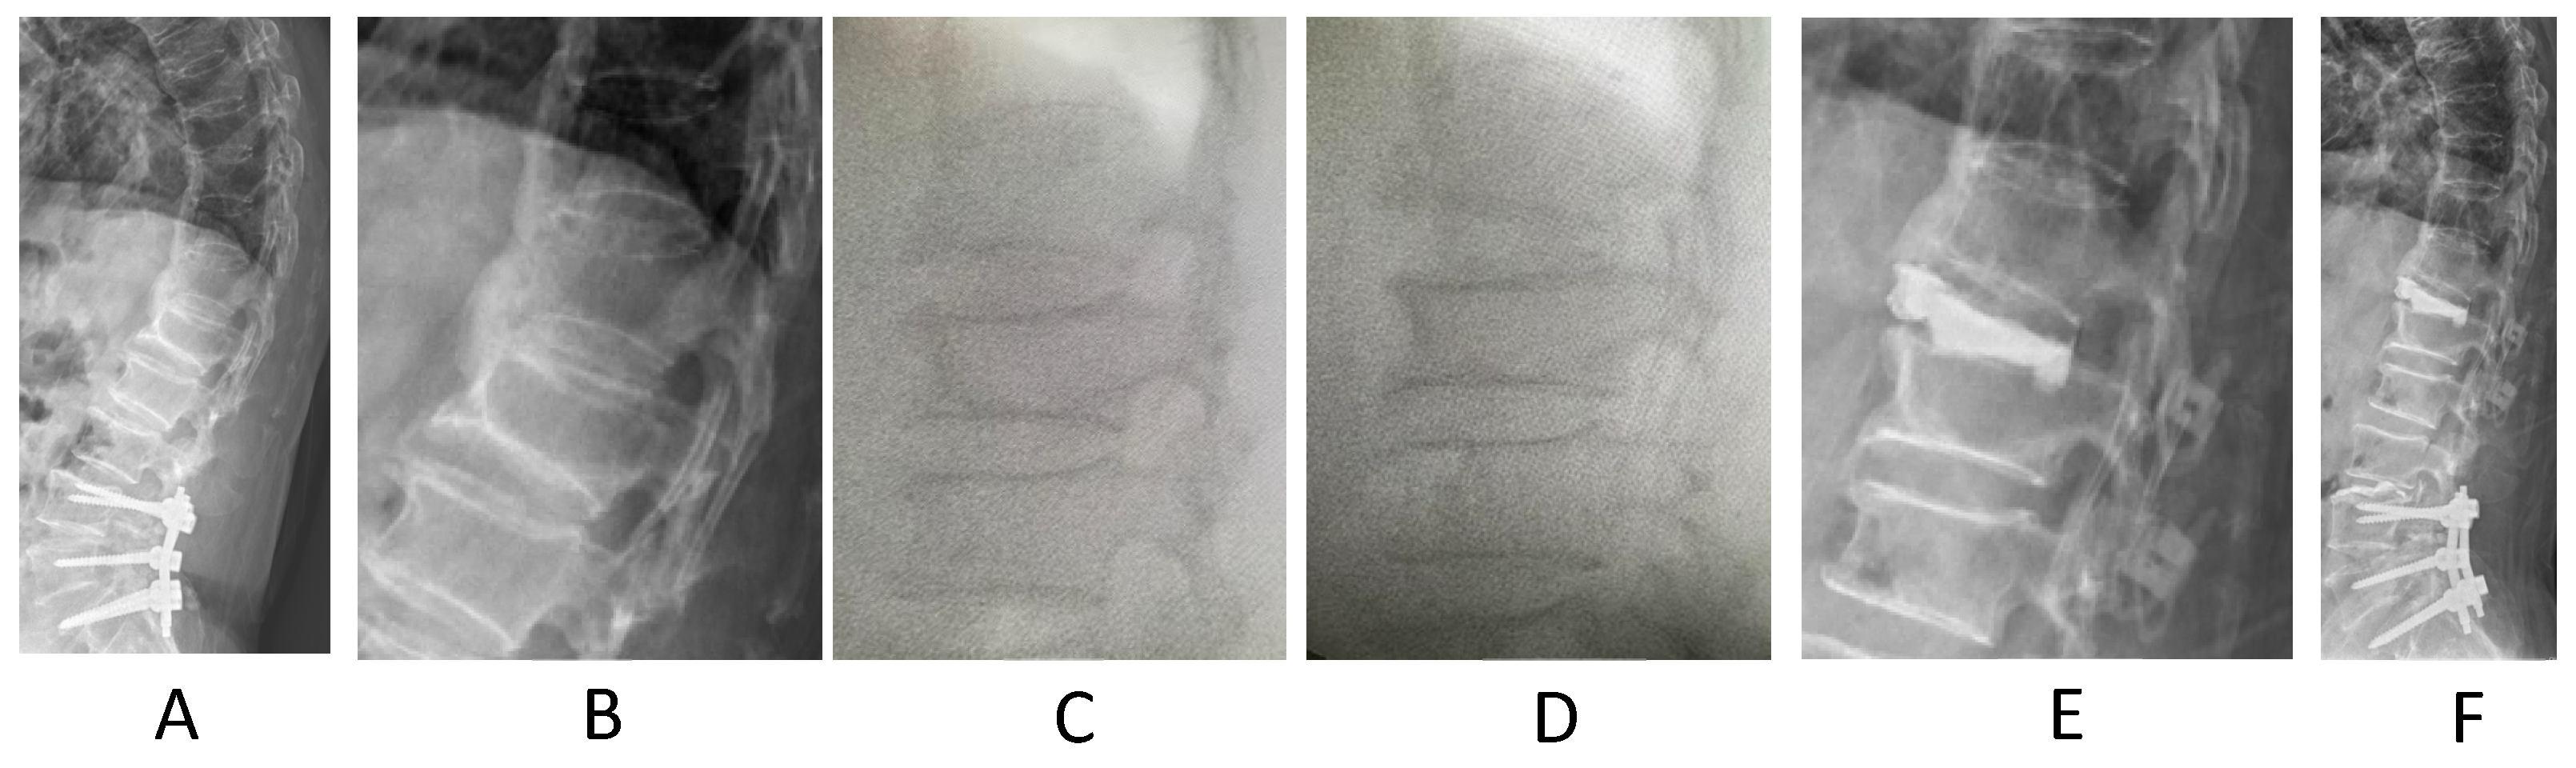

2. Materials and Methods

3. Results

4. Discussion